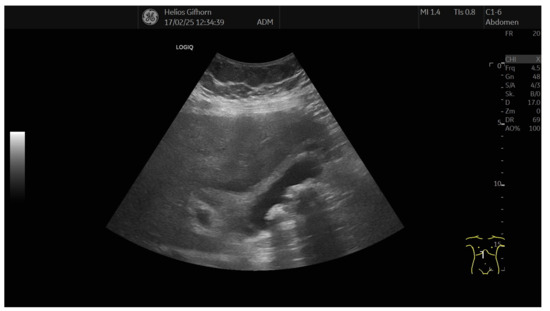

13.02: Abdominal ultrasound identified only gallbladder microlithiasis, without bile duct dilation (Figure 1).

Repeat ultrasound revealed discrete hilar ductal dilation.

Figure 1. Abdominal ultrasound (13.02.2025): gallbladder microlithiasis, no bile duct dilation.